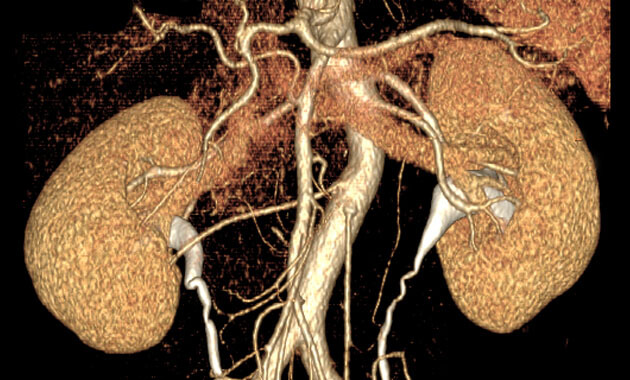

The Abdominal Imaging Division of the UC San Francisco Department of Radiology and Biomedical Imaging is made up of internationally recognized abdominal imaging experts who diagnose and treat disorders of the liver, pancreas, colon, uterus, ovaries, prostate, and bladder. The Abdominal Imaging Division is focused on serving patients, conducting research, and training the next generation of radiologists.

- Kidney cancer (including renal cancer)